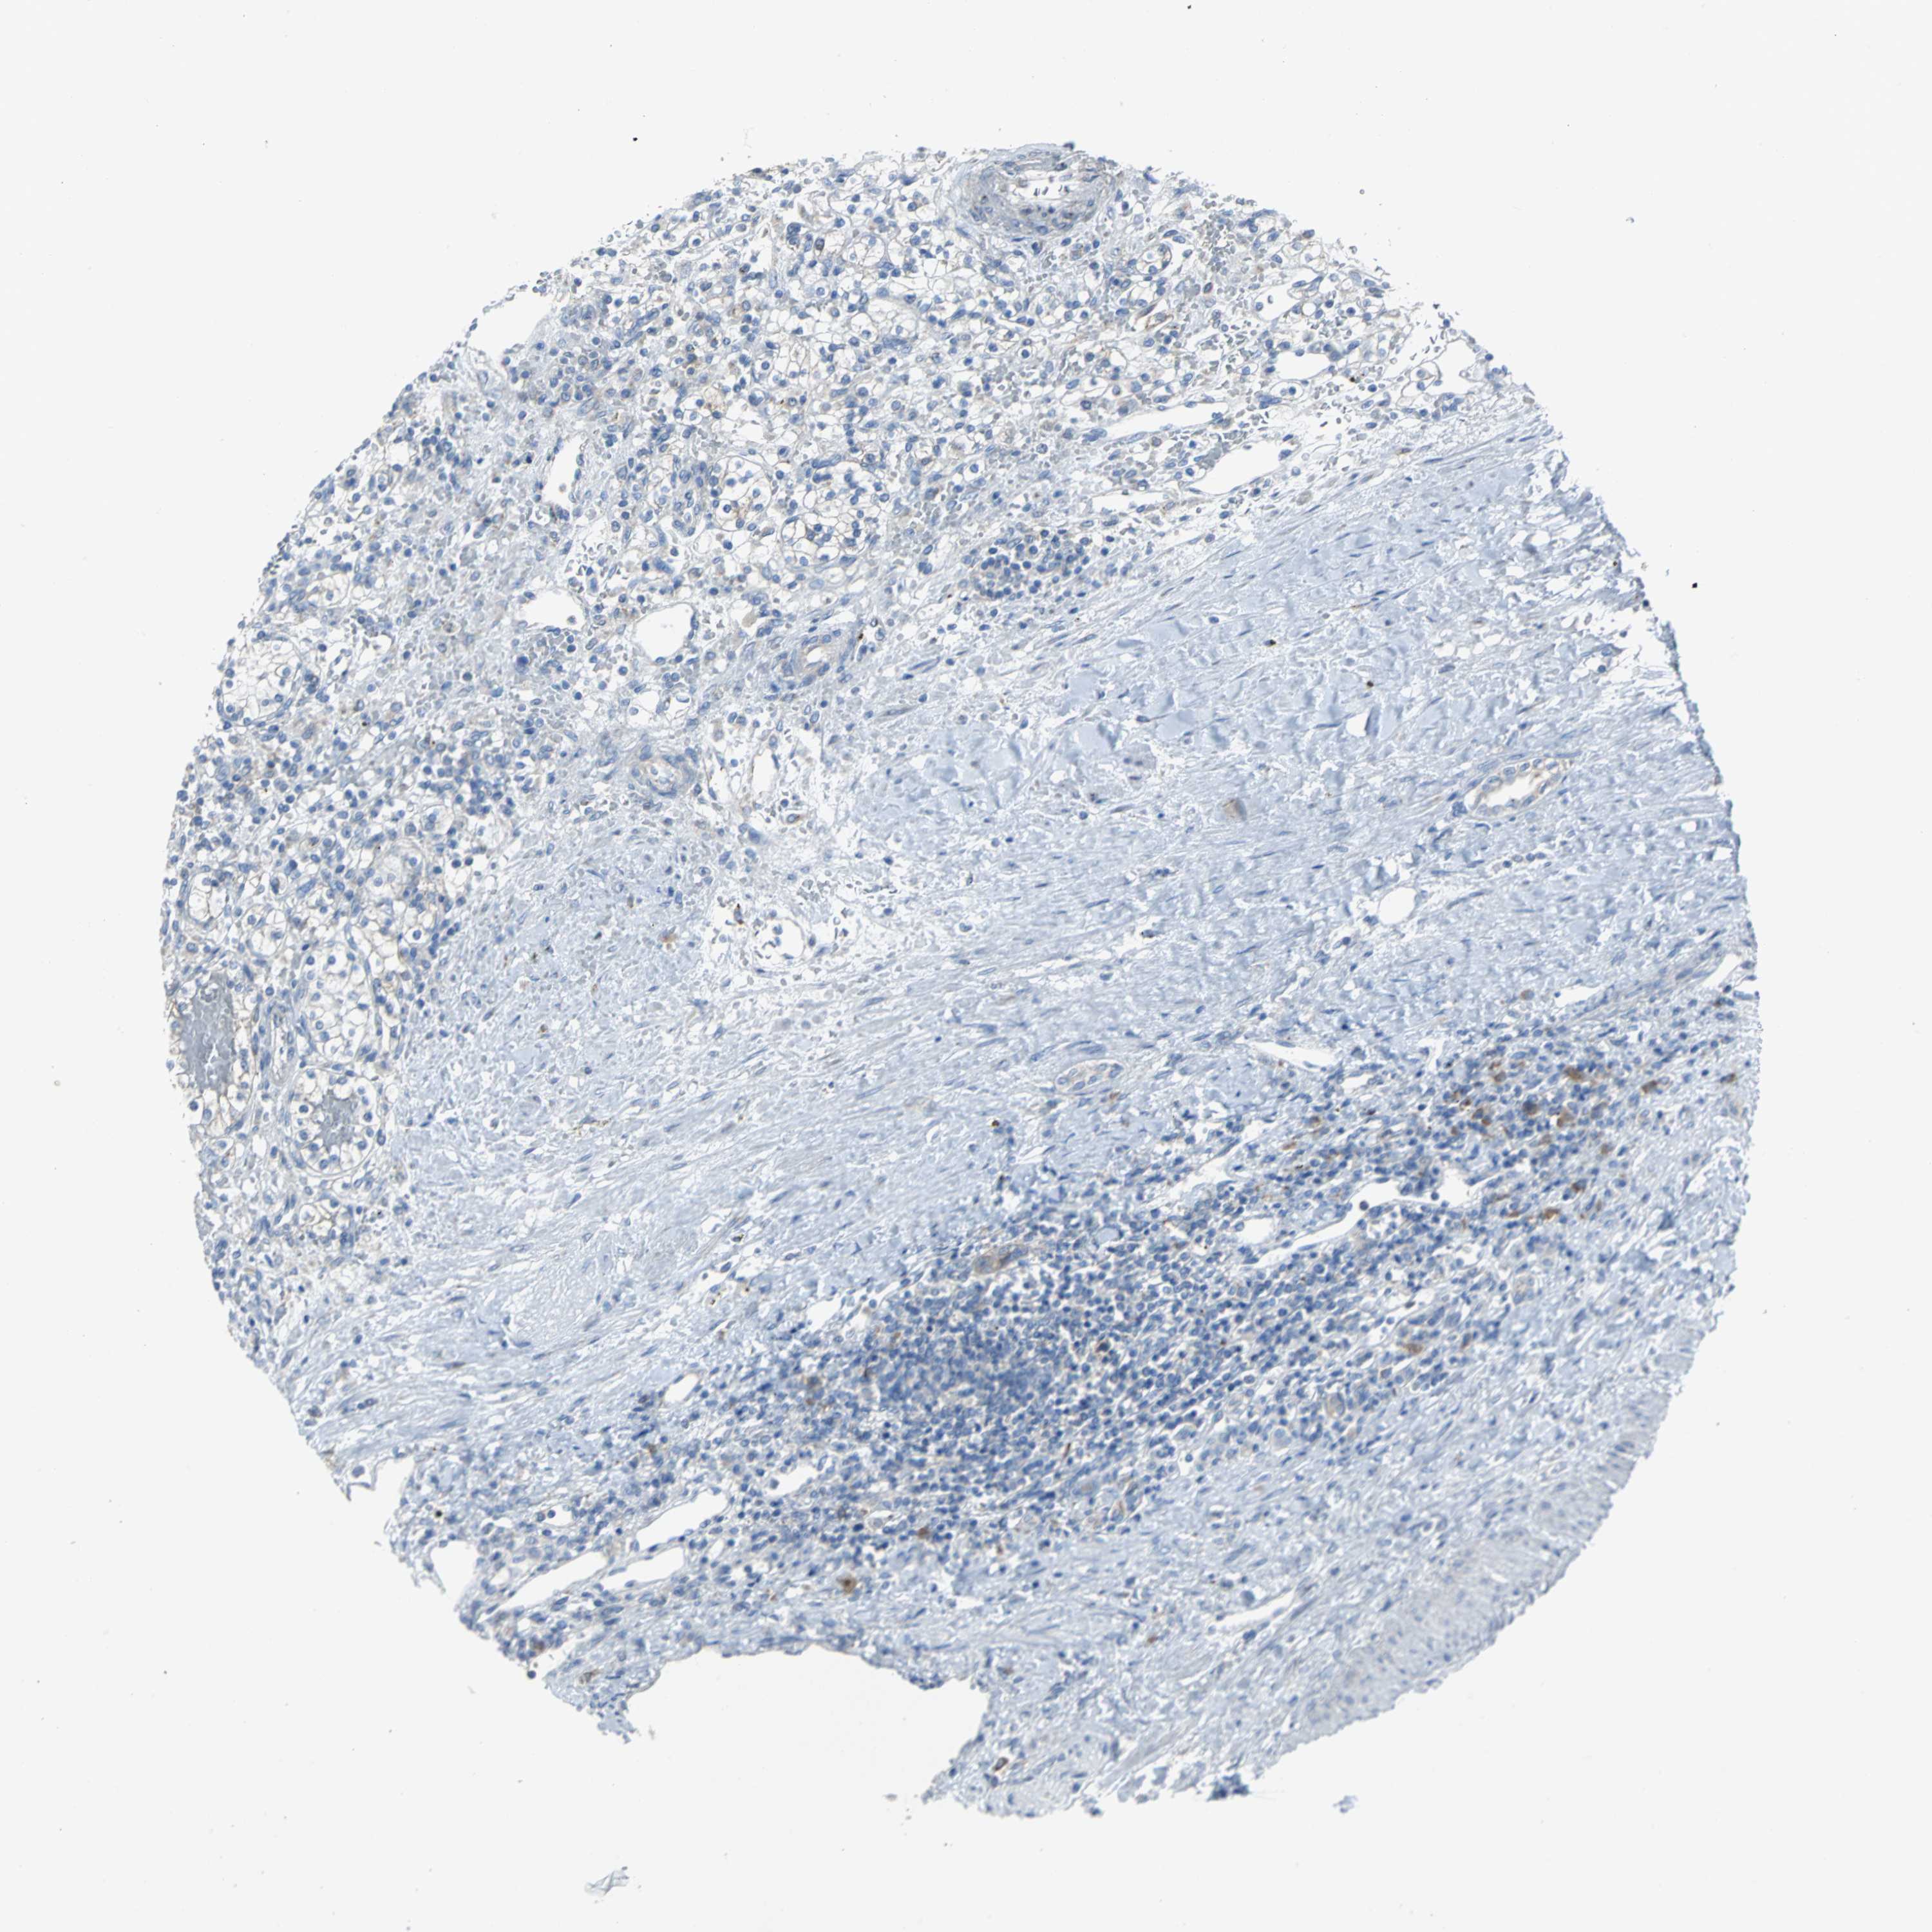

KIDNEY RENAL PAPILLARY CELL CARCINOMA (TCGA) - Interactive survival scatter ploti

The Survival Scatter plot shows the clinical status (i.e. dead or alive) for all individuals in the patient cohort, based on the same data that underlies the corresponding Kaplan-Meier plots. Patients that are alive at last time for follow-up are shown in blue and patients who have died during the study are shown in red.

The x-axis shows the expression levels (FPKM) of the investigated gene in the tumor tissue at the time of diagnosis. The y-axis shows the follow-up time after diagnosis (years). Both axes are complimented with kernel density curves demonstrating the data density over the axes. The top density plot shows the expression levels (FPKM) distribution among dead (red) and alive patients (blue). The right density plot shows the data density of the survived years of dead patients with high and low expression levels respectively, stratified using the cutoff indicated by the vertical dashed line through the Survival Scatter plot. This cutoff is automatically defined based on the FPKM cutoff that minimizes the p-score. The cutoff can be changed by dragging the vertical line or by entering a cutoff value in the square labeled "Current cut-off".

Under the Survival Scatter plot the p-score landscape (black curve; left axis) is shown together with dead median separation (red curve; right axis). Dead median separation is the difference in median mRNA expression between patients who have died with high and low expression, respectively. It is calculated as follows: median FPKM expression of dead patients with high expression - median FPKM expression of dead patients with low expression. This is intended to aid the user in visually exploring custom cutoffs and the associated p-scores and dead median separation.

Individual patient data is displayed and can be filtered by clicking on one or more of the category buttons on the top of the page. Categories describing expression level and patient information include: high, low, alive, dead, female, male and tumor stages. The scale of the x-axis can be toggled between linear and log-scale by clicking on the "x log" button. Mouse-over function shows TCGA ID, patient information and mRNA expression (FPKM) for each patient.

& Survival analysisi